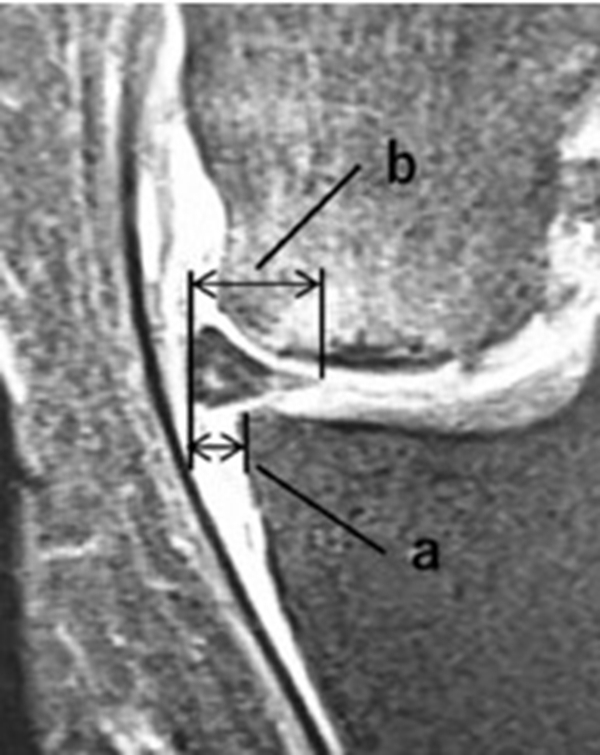

内侧半月板挤压(MME)以绝对值和挤压相对百分比 (RPE) 的形式呈现,其定义为挤压半月板宽度与整个半月板宽度相比的百分比

a.患者,59岁女性,AP侧位片显示SONKⅠ期,FTA<180°;b.MRI T2显示病变深度<20mm,患者出现症状1年后保守治疗;c.75岁女性,X线显示SONKⅠ期,FTA>180°;d. MRI T2显示病变深度>20mm,患者于症状出现后11周行手术治疗